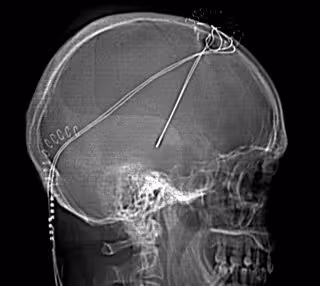

Tratamiento Parkinson